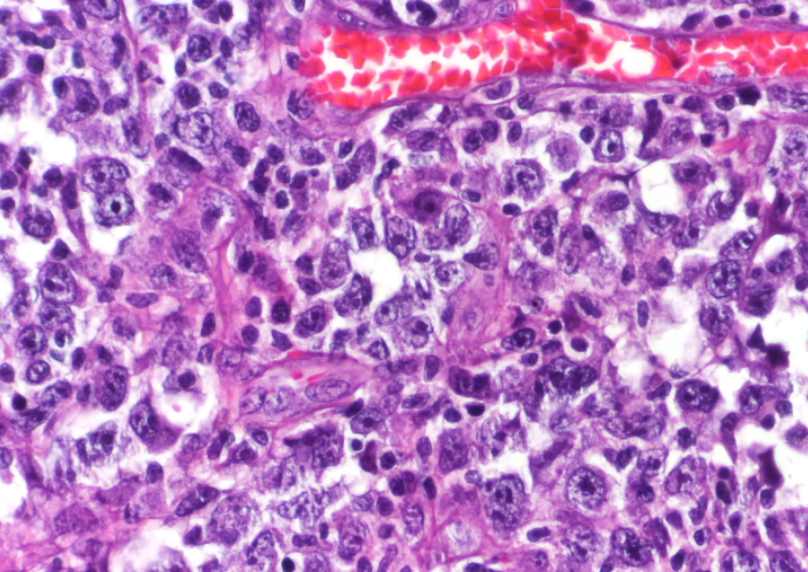

The approval was based on positive findings from the INO-VATE ALL clinical trial, which included 326 patients with Philadelphia chromosome-negative or Philadelphia chromosome-positive relapsed or refractory B-cell precursor ALL.

Patients had ≥5% bone marrow blasts and underwent 1 or 2 previous chemotherapy treatments for ALL. Patients with Philadelphia chromosome-positive disease were required to have failed therapy with at least 1 tyrosine kinase inhibitor and chemotherapy, according to the release.

Of the randomized patients treated with inotuzumab ozogamicin, 35.8% experienced complete remission (CR) with a median of 8 months. Additionally, 89.7% of these patients experienced minimal residual disease (MRD)-negativity, according to the study.

In contrast, only 17.4% of patients treated with chemotherapy experienced CR with a median of 4.9 months. The investigators reported that 31.6% of chemotherapy-treated patients achieved MRD-negativity.